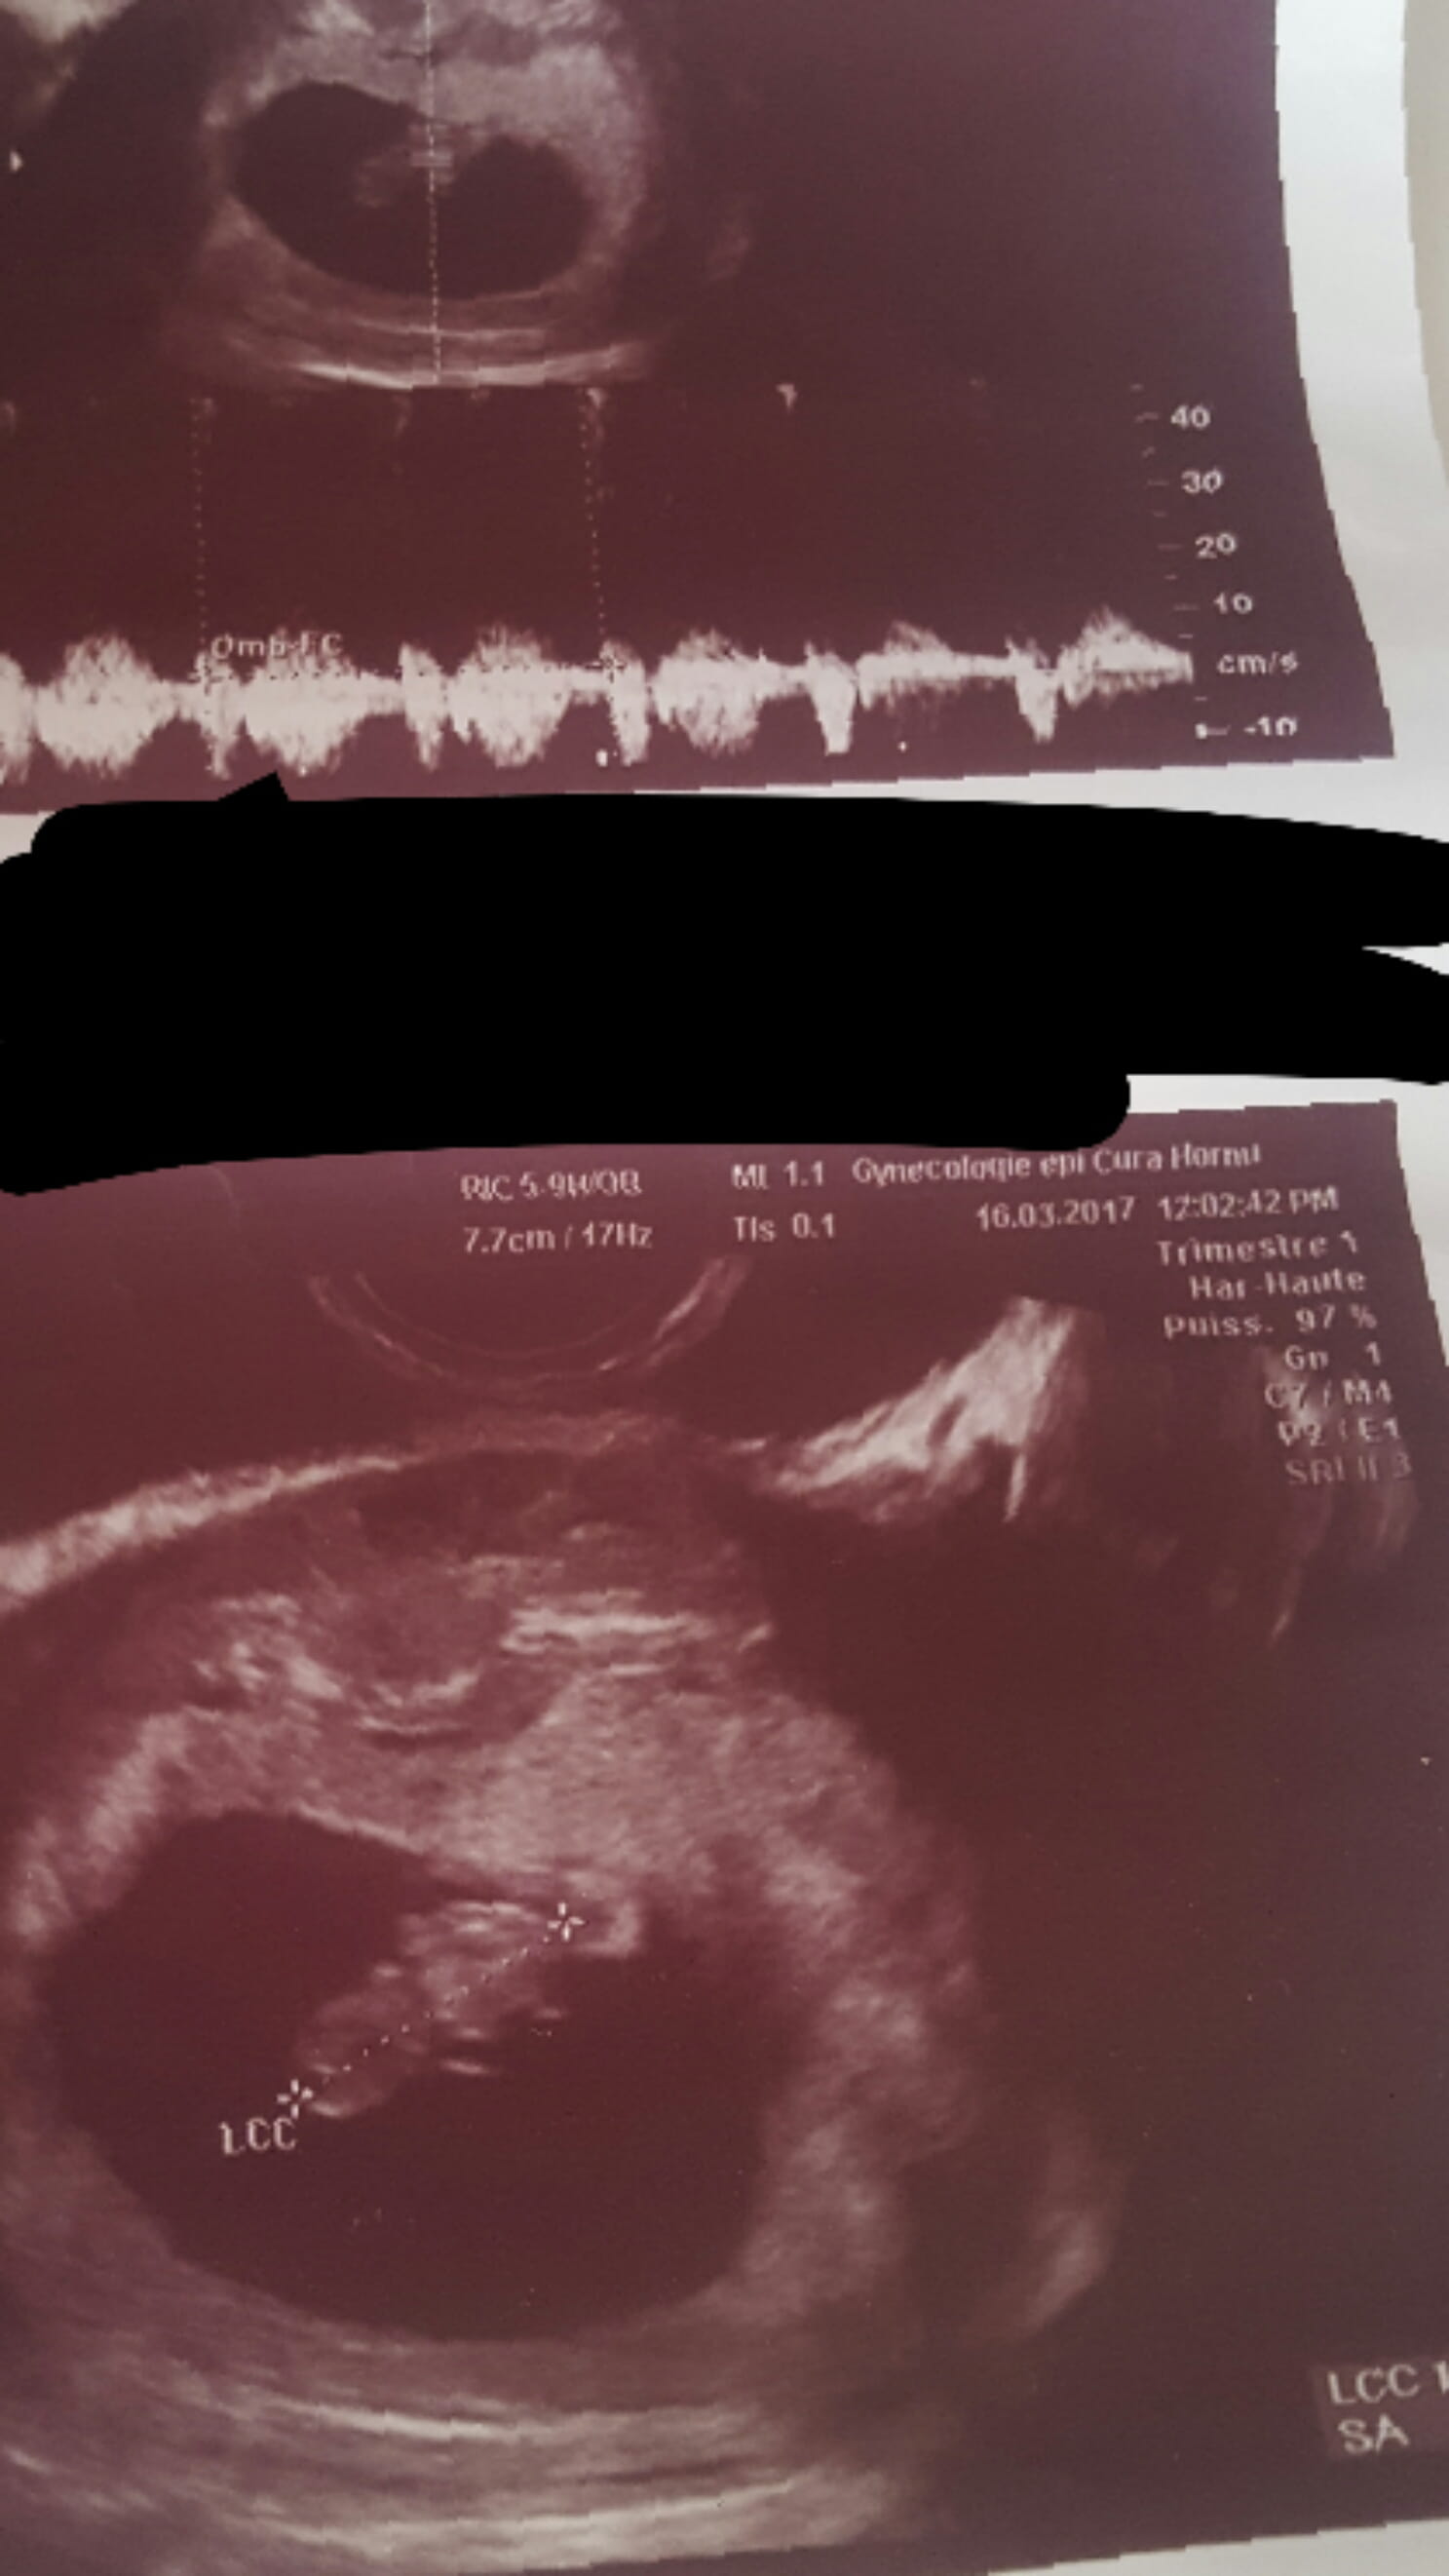

Comme eco j'ai celle dun 16 mars que j'ai quand été la première foix au gygy

Je les fait le 16 mars es.pas rdv avant le 21 avril pour les résultats